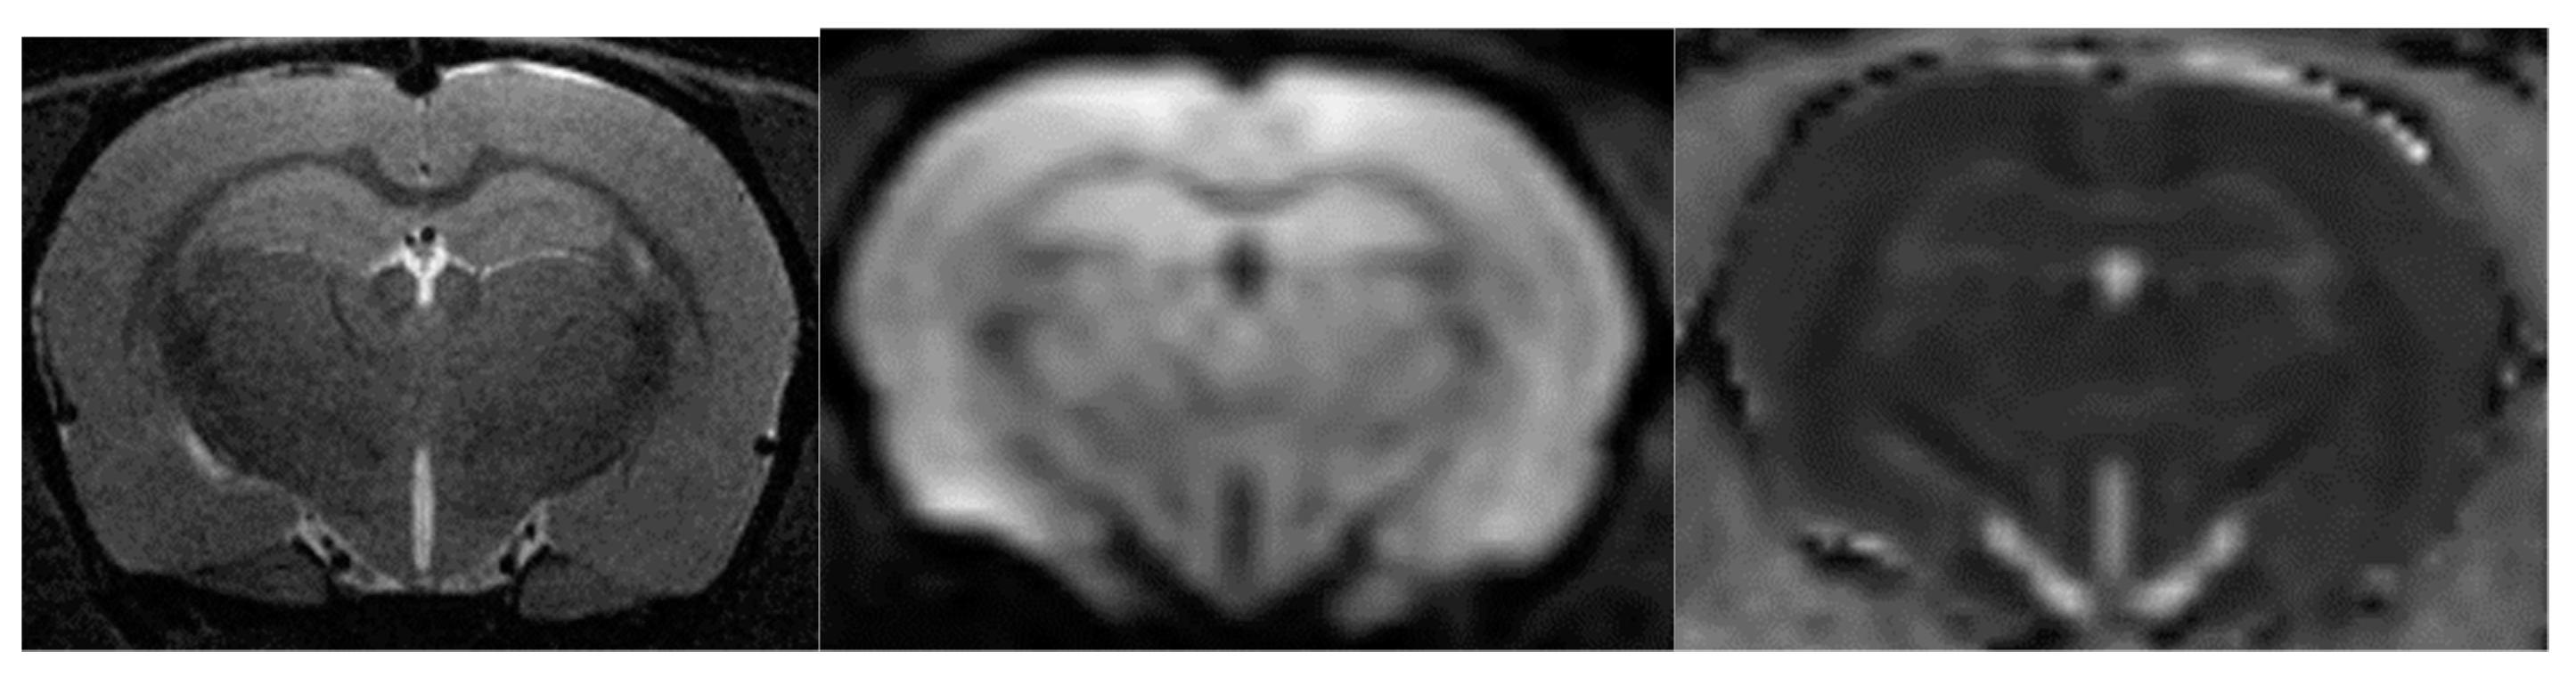

As with MRA, DWI was performed in one scan session with two other MRI techniques [58]. To obtain diffusion-weighted tomograms, a three-dimensional echo-planar pulse sequence was used with the following parameters: TE = 15.4 ms; TR = 2000 ms; the amount of excitation is 1, and the isotropic voxel size is 200 µm. The data were obtained using a multi-pass acquisition with five directions and three repetitions for b = 0, 100, 200, 500, 1000 s/mm2. DWI data processing with measured diffusion coefficient (ADC) estimation was performed using ParaVision 5.1, Image Sequence Analysis Tool, dtraceb function from Bruker sequence analysis library to generate average ADC for each ROI based on the equation: ADC = ln (S0/Sn)/bn, where S0 is an intensity of the T2-weighted image (b = 0), and Sn is an intensity of the diffusion-weighted image with bn as the decay factor of the diffusion gradient. This data processing step resulted in a parametric map of the numerical values of the measured diffusion coefficient. Eight brain slices with calculated ADCs were obtained; they anatomically corresponded to T2-weighted images in the Bregma range: from 1.2 mm to −3.4 mm). Please see Figure 16 for corresponding brain images.

Figure 16. From left to right are images of T2-WI, DWI, ADC.